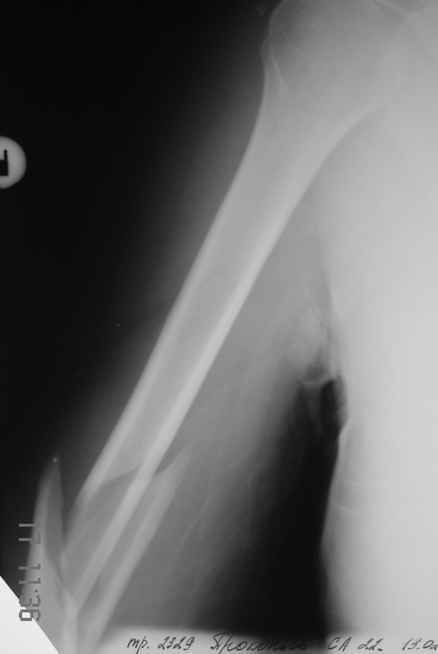

>антероградный - 30 процентов имеют боль в плече, связанную с повреждением ротаторной манжеты

Мы в последние годы все еще используем для переломов такой локализации эластичные титановые стержни (по мотивам ярославских разработок, Зверева-Ключевского). Такой стержень можно вводить не через сухожилие надостной мышцы, а дистальнее.

Снимки до, через 1 и 2 мес. после синтеза.